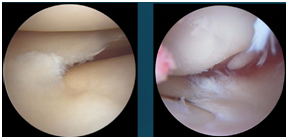

正常的半月板

损伤的半月板